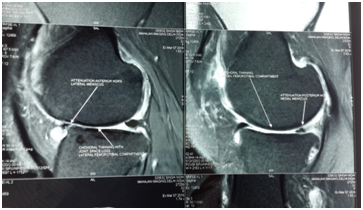

Biochemical test showed decreased level of ESR, CRP and Rheumatoid Titer. X-rays showed less Osteopenia. MRI of knee showed increased thickness in articular cartilage with reduction in synovial thickening and joint effusion. There was visible repair of articular cartilage breach Figures (4-6B).

Figure 4 (B) Post-stemcell transplantation.

Figure 5 (B) Post-stemcell transplantation.